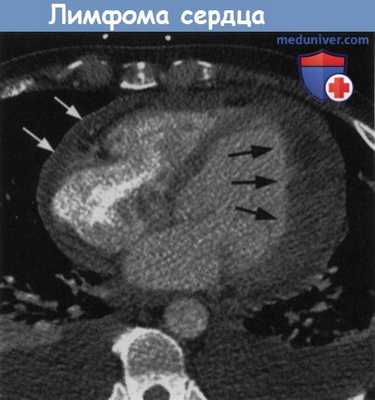

Начальная кардиальная пимфома у пациента с желудочковой аритмией.

Неоднородное утолщение боковой стенки левого желудочка (черные стрелки) из-за проникающего роста лимфомы.

Перикардиальный выпот (белые стрелки) и билатеральный плевральный выпот.